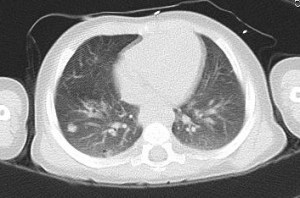

Here is what we are looking at. Imagine you sliced the top of his body off at the shoulders and then looked down “into” him and mirror-image what you see. For example, the half a potato shape on the far left is his right arm. The two misshapen black crescents facing each other are his lungs. The white football trophy in the middle is his heart on back to his spinal column. The bright white patches in the lungs are what we are watching, I believe. For all I can tell, they’ve been in every scan I’ve seen. The important part is they didn’t “glow” on the *PET scan.

*The PET scan is based on the body’s use of sugar. They “starve” him for 6 hours and then give him a sugary contrast solution. All the parts of the body that use the sugar will “glow” a bright color on the otherwise black and white scan. The brain, kidneys, and bladder, for example, will always glow because the use a lot of sugar. Cancer-type cells also use a lot of sugar, so docs look for abnormal glowing places.

UPDATE: The CT scan went well, and we were able to do it without sedation. The rounder white “blobs” are the lesions the doctor was watching. This particular slice of the scan doesn’t show the one remaining significant round, black “bleb” in his right lung. The bleb is like an air pocket caused, we think, by the chemo killing off the bad cells, leaving a weakened spot. Today, the scan showed that bleb was gone and in its place, a lesion, indicating to us that it is, indeed scar tissue. Other lesions had resolved or shrunk. The doctor was very pleased! He will see Elijah again for a checkup in a month, and will schedule a set of scans for three months from now. If the next set of scans look good, we will talk about removing his port.